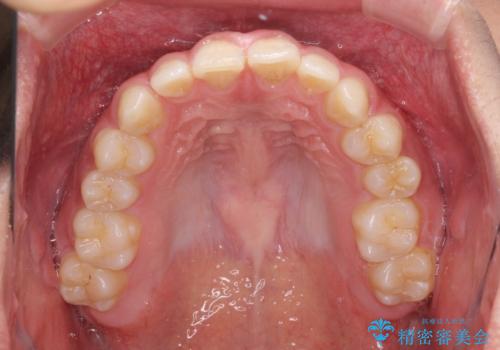

隙間とデコボコを治したい ワイヤー装置による矯正治療

- 前歯のデコボコと隙間を気にして来院された患者様です。

治療手段としてはワイヤー装置でもインビザラインでも可能でしたが、インビザラインの自己管理は自信がないとのことで、ワイヤー矯正により隙間を閉じていくこととしました。

隙間の原因は舌の突出癖であったので、舌癖改善のためのトレーニングを指導しながら治療を進めて行くこととしました。

舌の突出癖がなかなか改善されず、治療開始時よりも隙間が大きく開いてしまう時期がありましたが、最終的にしっかりと閉じて終了することができました。